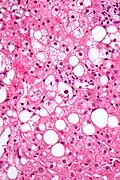

Mallory bodies are classically found in the livers of people suffering from alcohol-induced liver disease and were once thought to be specific for that.[2]

They are most common in alcoholic hepatitis (prevalence of 65%) and alcoholic cirrhosis (prevalence of 51%).[3]

Mallory bodies are highly eosinophilic and thus appear pink on H&E stain. The bodies themselves are made up of intermediate cytokeratin 8/18 filament proteins that have been ubiquitinated, or bound by other proteins such as heat shock proteins, or p62/Sequestosome 1.[5]